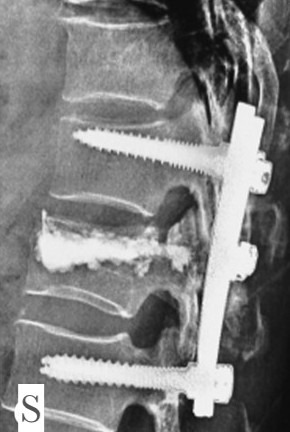

Gallery

Explore our advanced spine care visuals.